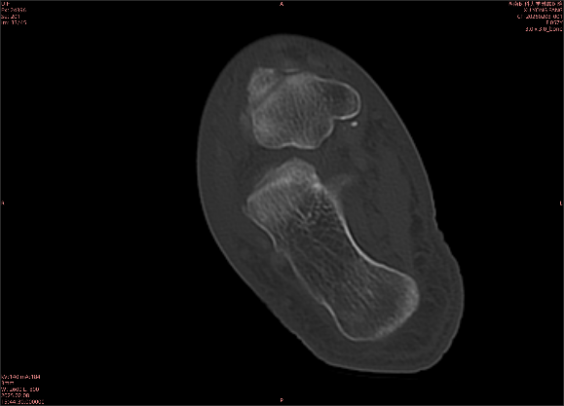

由于無(wú)骨皮質(zhì)中斷,尚不足以引起X線衰減系數(shù)的明顯改變,X線平片無(wú)異常征象;CT在顯示骨皮質(zhì)及軟組織異常方面明顯優(yōu)于傳統(tǒng)X線,特別是三維重建能夠有效的評(píng)價(jià)復(fù)雜骨折,骨外傷CT檢查應(yīng)用廣泛,但CT對(duì)隱性骨折的顯示亦極為有限。

舉例圖像

圖2

專業(yè)解釋看不懂沒(méi)關(guān)系,大家看圖1和圖2就可以了,這是同一個(gè)患者跟骨的磁共振和CT圖像,圖1的紅色箭頭指示的黑線就是磁共振圖像顯示的骨折線,一目了然。而對(duì)比圖2的CT圖像上并未顯示異常。